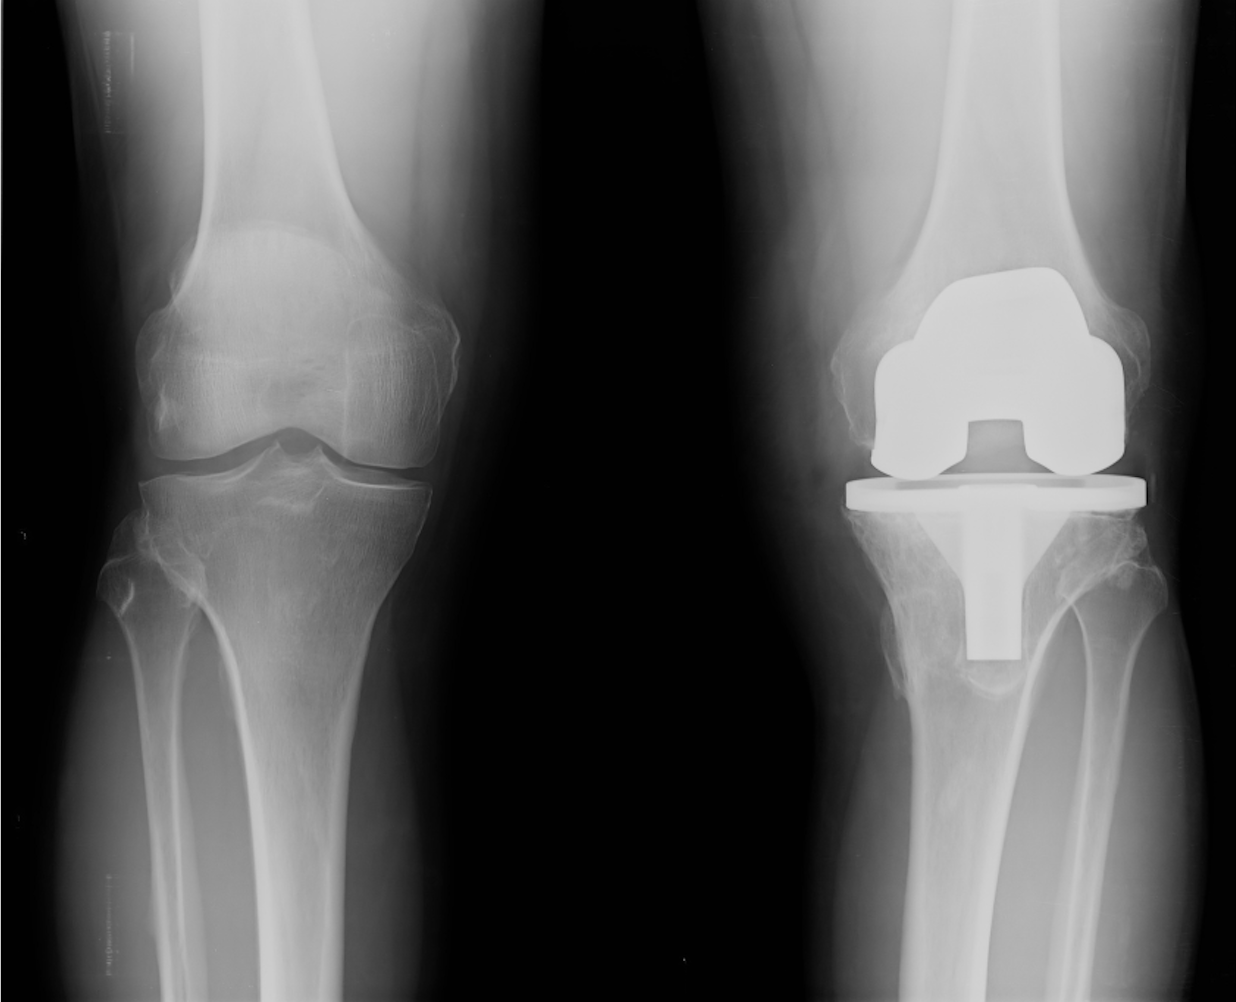

Revision Hip & Knee Clinic

Are you having problems with your joint replacement? Whether it’s worn out or has just never been right, we offer a comprehensive consultation and assessment to establish the right diagnosis. Our surgeons are experts in hip and knee replacement and can advise you on treatment options specific to your individual case. Get in touch, we are here to help.